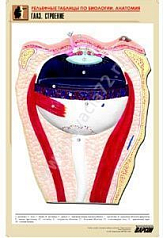

Комплект включает в себя 21 таблицу следующего содержания:

6. Глаз. Строение;

Изделие соответствует Перечню средств обучения и воспитания, утвержденному Приказом Минобрнауки России N 804 (подраздел «Демонстрационные учебно-наглядные пособия для профильного медико-биологического класса»).